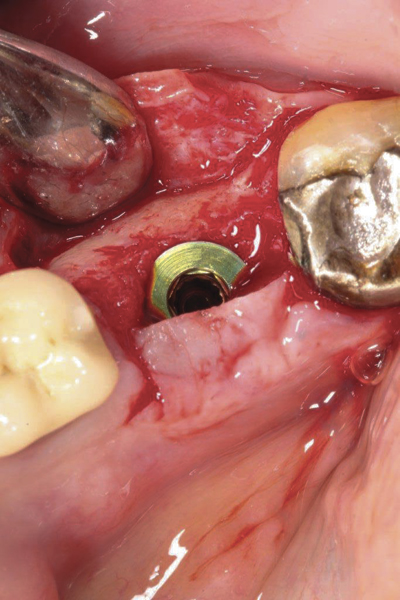

Fig 1. (Case 1) Tooth No. 19 manifested a buccal fistulous tract. Probing depth on the buccal was 8 mm.

Figure 1

Case Presentations

The four presented cases shown in Figure 1 through Figure 25 were all treated in a similar manner as outlined in detail in the captions for the first case (Figure 1 through Figure 11). In all four cases, teeth with pathosis were removed, buccal and lingual flaps were elevated, and sites were surgically debrided. A Cytoplast d-PTFE barrier was sized and inserted usually under the buccal flap, the bone graft was added, the barrier was then tucked under the lingual flap, and the flaps were sutured. Bone grafts were used in all of the cases, because buccal bony plates were resorbed and the bone graft helped support the barrier.